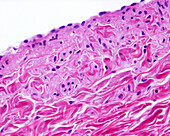

13613516 - Vein adventitia, light micrograph